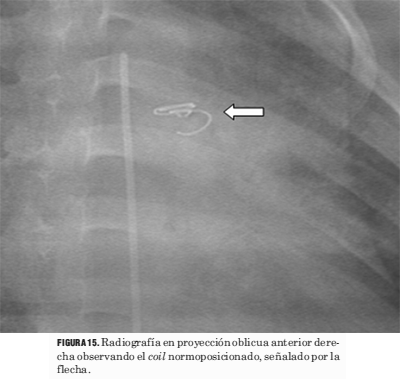

Por último, debemos recordar que con el uso de esta tecnología se han agregado nuevos elementos a valorar en la lectura de la radiografía de tórax (figuras 14 y 15).

Figura 15. Radiografía en proyección oblicua anterior derecha observando el coil normoposicionado, señalado por la flecha.